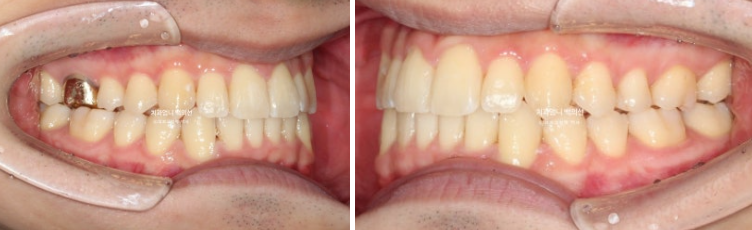

24.09

앞니 중심선 불일치가 많이 좋아졌으나 아직 완벽히 맞지는 않습니다.

어금니 교합도 교합관계 자체는 1급으로 좋아졌으나 위아래 틈이 보입니다.

교합과 중심선을 좀 더 개선하고자 추가장치 재제작에 들어갔습니다